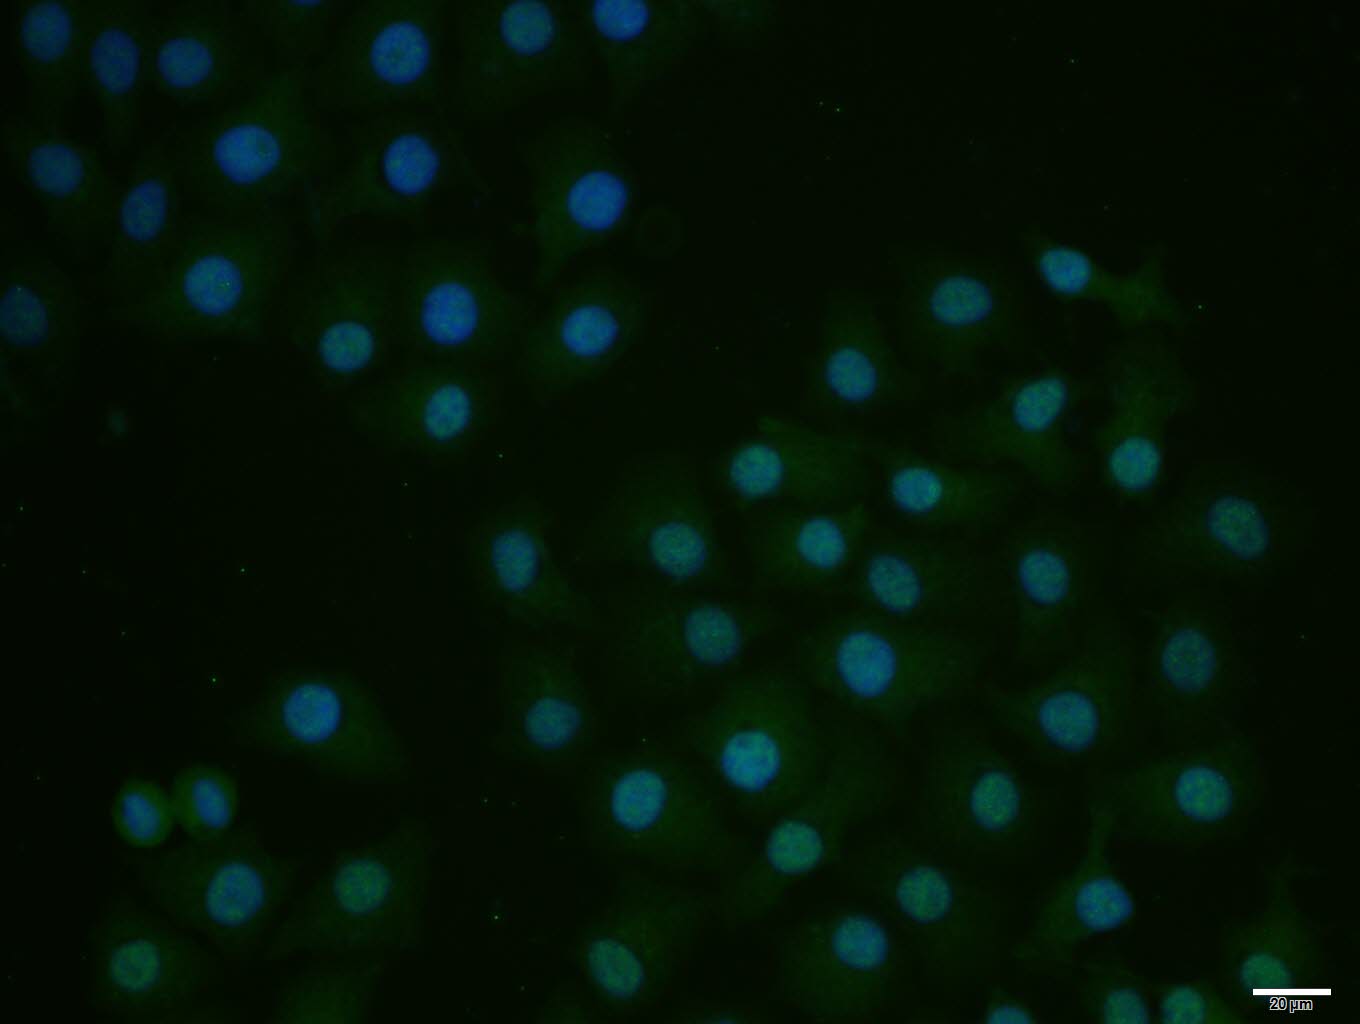

HepG2 cell; 4% Paraformaldehyde-fixed; Triton X-100 at room temperature for 20 min; Blocking buffer (normal goat serum, C-0005) at 37°C for 20 min; Antibody incubation with (E2F1) polyclonal Antibody, Unconjugated (bs-0599R) 1:100, 90 minutes at 37°C; followed by a conjugated Goat Anti-Rabbit IgG antibody at 37°C for 90 minutes, DAPI (blue, C02-04002) was used to stain the cell nuclei.